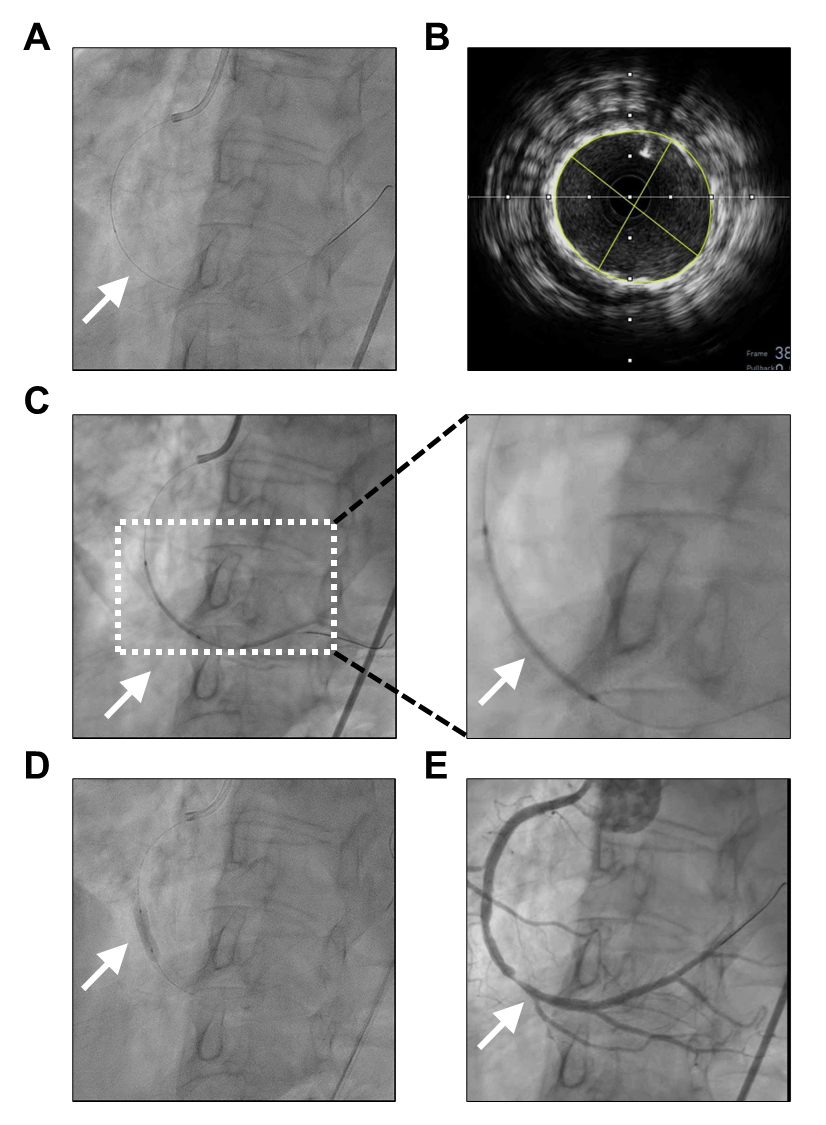

The patient was transferred to the cardiac catheterization laboratory within 25 minutes of symptom onset. Vascular access was obtained via the right femoral artery using a 7 Fr sheath. A JR 4.0 guiding catheter was used to engage the right coronary artery (RCA). Angiography revealed a total occlusion of the distal RCA(Figure 1), consistent with the culprit lesion for the inferior STEMI. Additional findings included diffuse 60–70% stenosis in the left circumflex artery (LCX) and a milking effect with up to 50% narrowing in the mid-left anterior descending artery (mLAD).

As show in the Figure 2, A SION Blue guidewire was advanced into the posterior left ventricular (PLV) branch of the RCA. Thrombus aspiration was performed using an Eliminate aspiration catheter, which successfully restored distal flow to TIMI grade 3. A 3.5 × 33 mm Xience sp drug-eluting stent was then deployed at the site of occlusion. Due to suboptimal stent expansion on initial angiography, post-dilatation was performed using a 4.0 × 15 mm Raiden balloon .

Intravascular ultrasound (IVUS) confirmed proper stent apposition and full expansion. No residual dissection or thrombus was noted. The final angiogram demonstrated complete restoration of blood flow in the RCA, with no procedural complications(Figure 3).

Key procedural details are summarized in Table 2. The intervention was performed efficiently with successful restoration of TIMI 3 flow and no procedural complications. Intravascular ultrasound was used to guide post-dilatation and confirm optimal stent deployment.

Figure 2. Sequential coronary angiographic images demonstrating the stages of stent deployment in the distal right coronary artery (dRCA). (A) SION blue-intervention image. (B) IVUS image. (C) Stent deployment using a 3.5 × 33 mm drug-eluting stent (white arrow). (D) Balloon inflation during post-dilatation (white arrow). (E) Final angiogram confirming restored 1 flow and well-expanded stent (white arrow).